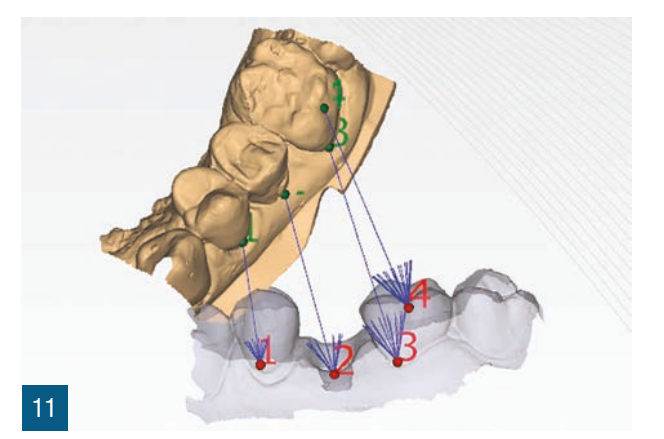

Пацієнтка 36 років звернулася до нас з частковим переломом коронки другого премоляра праворуч (1.5). Після перевірки неможливості консервативного відновлення було заплановано імплантно-протезне лікування з негайною екстракцією для заміни ураженого елемента (Рис. 1,2). Пацієнтка, не курець, була класифікована як ASA 1. Було виконано локалізовану CBCT в ураженій області для перевірки наявності та морфології вестибулярної кісткової стінки навколо елемента, що підлягає екстракції, в альвеолярному відростку. Перед екстракцією 1.5 була виконана цифрова внутрішньоротова відбитка (iTero Flex, Align Technology) зуба та прилеглих ділянок (Рис. 3). Після плескальної анестезії була виконана екстракція, обмежуючи травму пародонтальних тканин, розділяючи корені та використовуючи міні-важелі та синдесмотоми для збереження вестибулярної кісткової пластини. Оцінюючи цілісність альвеоли та сприятливі анатомічні умови, переходять до встановлення імплантату розмірів, що забезпечують адекватну первинну стабільність (4.1 x 11,5 TSVH ZimmerBiomet). Імплантат розміщується в близькій до піднебіння позиції відповідно до вказівок літератури (Рис. 6,7), заповнюючи проміжок між імплантатом та вестибулярною кістковою кортикою за допомогою гетерологічної кісткової пересадки (Copioss Zimmer-Biomet). Монтажний пристрій формують так, ніби це абатмент, і після його закручування на імплантаті проводять сканування. З цифрового внутрішньоротового сканування виконується CAD проектування гвинта загоєння (Рис. 4). У проекті буде використано як передекстраційне сканування, так і сканування з монтажним пристроєм, перетвореним в абатмент, щоб максимально точно відтворити гвинт загоєння. Морфологія гвинта загоєння відтворить існуючі тканинні умови на момент хірургії та дозволить уникнути естетичних дефектів у рожевій естетиці. Завершивши цифрове проектування, виконується 3D-друк з смоли (Lab2 Formlab) кастомізованого гвинта загоєння. Після завершення друку, отриманий гвинт загоєння з смоли Nextdent цементується з авто- та фото-твердим смолистим цементом (Relix Unicem, 3M) до абатмента, отриманого з монтажного пристрою, а потім закручується на імплантат (Рис. 5,6). Було проведено рентгенологічні контролі через три місяці та через рік (Рис. 7,8). Через 3 місяці була виготовлена остаточна коронка через цифровий потік з тим самим сканером та спеціальними сканбоді (Gentek, Zfx), які дозволяють ідентифікувати точне просторове положення імплантату. Через тиждень була передана остаточна монолітна коронка з фарбованої цирконії, закручена на ti-base (Рис. 9,10). Через рік було виконано ще одне сканування для оцінки з часом можливих об'ємних змін періімплантних тканин. Сканування, виконані на етапі передекстракції та через рік, були оброблені за допомогою спеціалізованого програмного забезпечення (meshlab) для оцінки розмірних змін (Рис.11-13).

У зв'язку з клінічними цілями, описаними Тарновим та співавторами, з цього клінічного випадку видно, як одночасна стабілізація кісткового сайту та заповнення існуючого зазору гетерологічним матеріалом дозволяє зберегти горизонтальні та вертикальні об'єми постекстракційного сайту. Швидкість і легкість виконання кастомізованого загоювального гвинта за цією методикою дозволяє покращити герметичність трансмукозного шляху та зберегти морфологічні та об'ємні характеристики до екстракції. Якщо використовувати неанатомічні загоювальні гвинти більшого діаметра, ми, безумовно, отримаємо кращу герметичність у порівнянні з класичними стандартними загоювальними гвинтами, але вони не дозволять точно відтворити межі постекстракційного сайту, як кастомізований загоювальний гвинт, отриманий за аналоговою та/або цифровою методикою. Цифровізація дозволяє суттєво скоротити час виконання та забезпечити більшу персоналізацію отриманого виробу. Точне відтворення існуючої ситуації, ймовірно, може гарантувати імпланту меншу кількість обслуговуючих втручань, таких як закручування та відкручування, на етапах проби. Цей клінічний випадок пропонує, як стабілізація періімплантних тканин може забезпечити оптимальне загоєння та зрілість тканин, спрощуючи фінальні етапи протезування. Це може дозволити уникнути подальших втручань для управління періімплантними тканинами, таких як повторні хірургії, пересадки та використання тимчасових конструкцій. Етап CAD дозволяє точно відтворити профільEmergence, копіюючи форму шийки зуба. Крім того, слід врахувати, що аналогове виготовлення загоювального гвинта вимагає простоїв, які можна використовувати для інших цілей, і тому в управлінні під час операції прискорюється робочий процес і досягнення кінцевого результату. Використання цифрових сканувань до та після хірургії дозволило порівняти об'єми періімплантних тканин, накладаючи сканування до та після хірургії через три місяці та через рік, щоб виявити об'ємні зміни. Це корисний інструмент для можливих клінічних оцінок, а також для комунікації з пацієнтом.